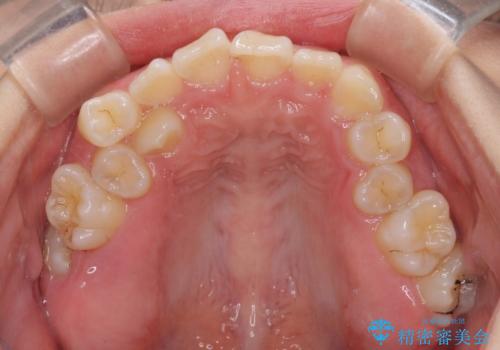

- 内側に生えている歯や埋もれた奥歯を気にして来院された患者様です。

顎の骨が小さいため、歯列が収まりきらずに叢生や未萌出となっている状態でした。

埋もれた奥歯を萌出させ、さらにデコボコを解消するために、上下左右の第1小臼歯4本に加え、親知らず4本も抜歯し、ワイヤー装置にて矯正治療を行うこととしました。

親知らずの抜歯により埋もれた奥歯周辺の歯肉が切除され、矯正装置が装着できるようになりました。

奥歯の移動、特に下顎大臼歯の移動は時間がかかることが多く、3年以上の治療期間を想定していましたが、想像以上に動きがよく、2年強で終えることができました。